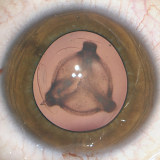

verschiedene Stadien einer Katarakt

Heute kann man mit einer in der Regel komplikationslosen, ambulanten Operation in örtlicher Betäubung eine erhebliche Verbesserung des Sehvermögens erreichen. Bei den allermeisten Star-Operationen wird nach Entfernen der eigenen getrübten Linse eine künstliche Linse (Intraokularlinse) eingesetzt. In Einzelfällen kann auch eine Sonderlinse zum Ausgleich höherer Hornhautverkrümmungen sinnvoll sein, auch die Alterssichtigkeit kann teilweise reduziert und damit eine gewisse Brillen-unabhängigkeit erreicht werden. Über Kosten, und wann dies Sinn macht, sollte individuell beraten werden.